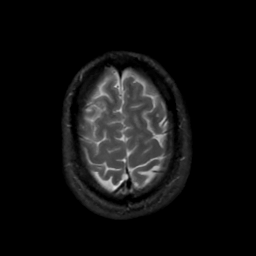

MR Study #4, March 3, 1991 -- Slice #43

[Home][Help][Clinical][Tour 1][Tour 2] Slice 43